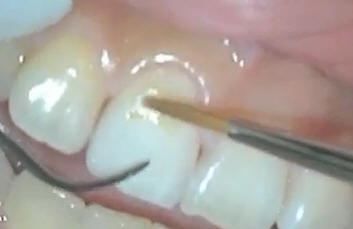

Los hombros en esmalte

son muy marcados |

Con una punta de oxido

de aluminio se redondea el hombro y se pule para una mejor

adaptación de la porcelana |

Levando el hombro

a subgingival solo en vestibular |

Con puntas de diamante

de grano extrafino se elimina el esmalte sin soporte en mesial y distal |